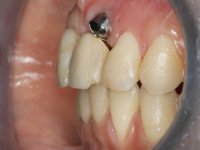

Paciente do sexo feminino, com 30 anos de idade, não fumadora. A paciente surge na consulta após tratamento ortodôntico e colocação de um implante no local do dente 2.1. Apresentava os dentes 3.7, 3.6 e 4.7 com tratamento endodôntico e os dentes 1.5, 2.5, 2.6 e 4.5 com restaurações extensas. Apresentava um periodonto fino e mostrava uma higiene oral satisfatória. Após exposição cirúrgica do implante este mostrou-se posicionado de forma inadequada. A reabilitação protética do implante mostrou-se impossível adotando critérios estéticos aceitáveis. A paciente durante 6 anos andou com uma coroa provisória de acrílico sobre um coto aparafusado como solução de recurso já que não aceitou a proposta de remover o implante. Após este tempo surge na consulta com um abcesso no dente 1.1. Analisada a situação constatou-se que os dentes 1.1 e 2.2 tinham extração indicada e o implante deveria ser removido ou submergido.

Na fase inicial, foi proposto à paciente fazer a exposição cirúrgica do implante e após avaliação clínica tomar decisões protéticas. Colocado o parafuso de cicatrização e feita a cicatrização dos tecidos moles, foi constatada uma posição inadequada do implante. Perante o dramatismo da situação foi proposto à paciente a remoção do implante e após regeneração tecidular colocar um novo implante. Esta proposta foi recusada pela paciente e foi sugerido por esta a reabilitação provisória do implante. Nesse sentido foi então feita nova proposta, desta feita, reabilitando o implante. Foi sugerido a confeção de um coto aparafusado e sobre este a colocação de uma coroa de acrílico com componente coronário e gengival. Passados 6 anos com o tratamento provisório a paciente surge na consulta com um abcesso no dente 1.1. Feita a análise clínica e imagiológica decidiu-se extrair os dentes 1.1 e 2.2, submergir o implante, colocar dois implantes no local dos 1.1 e 2.2 e fazer regeneração tecidular adequada. A temporização seria feita com uma ponte provisória de 3 elementos aderida com uma rede aos dentes vizinhos. Após osteointegração seria reabilitada definitivamente com uma ponte de 3 elementos, com infraestrutura de Zr revestida a cerâmica.

A exposição cirúrgica do implante e a colocação do parafuso de cicatrização mostrou-se uma surpresa negativa no que diz respeito à sua posição. Rejeitada a proposta de remoção do implante, avançamos para a sua reabilitação provisória. Foi feita a impressão por técnica de moldeira aberta e em laboratório foi confecionado um coto aparafusado com componente gengival e coronário e uma coroa em acrílico também com estes dois componentes. A coroa provisória foi colocada em boca até ser tomada uma decisão definitiva. Passaram 6 anos até que a paciente retorna à consulta com um abcesso no dente 1.1. Tomada a decisão de extrair os dentes 1.1 e 2.2 foi feita uma impressão para confecionar uma ponte provisória de 3 elementos com uma rede para ser aderida aos dentes adjacentes. A cirurgia foi planificada e realizada, colocando-se os dois implantes no local do 1.1 e 2.2 e o implante no local do 2.1 foi cortado com o objetivo de o submergir, simultaneamente foi feita a regeneração tecidular adequada (Trabalho Cirúrgico realizado por Dr. Manuel Neves). Durante a osteointegração a paciente utilizou a ponte provisória fixa. Foi realizada primeira impressão para a confeção de uma ponte provisória aparafusada em Zr que trabalhou durante 12 semanas os tecidos moles. A impressão definitiva foi feita com a individualização dos transferes. A reabilitação definitiva foi feita com cotos ceramizados e com uma ponte de infraestrutura em Zr revestida por cerâmica. Em virtude da inclinação do implante colocado no local do dente 1.1 a ponte exigiu fixação cimentada.